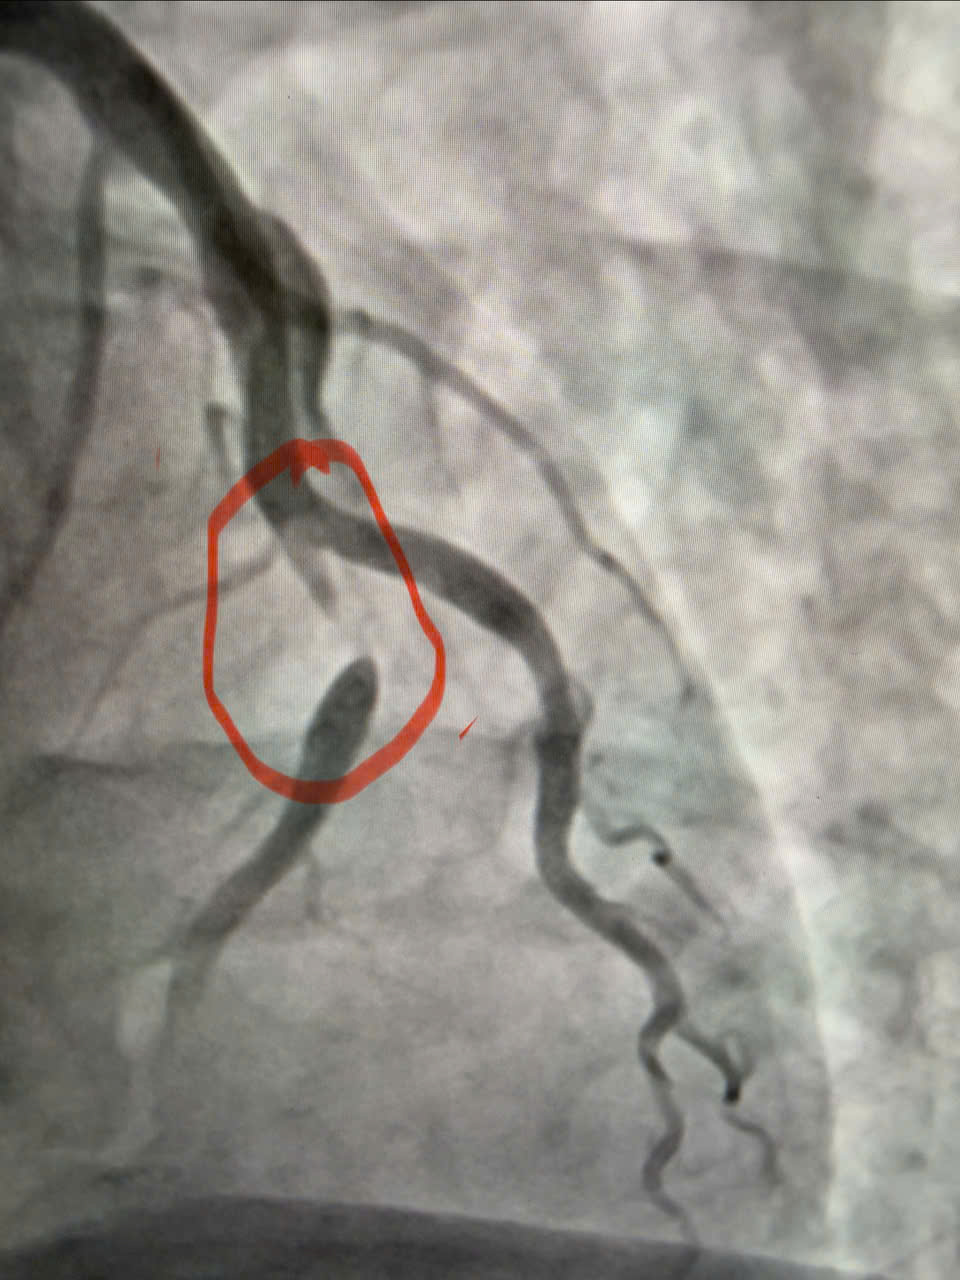

Hình ảnh động mạch vành sau can thiệp đặt stent, dòng máu nuôi cơ tim được tái thông tốt.

Ê-kíp bác sĩ Khoa Nội Tim mạch đã tiến hành chụp động mạch vành, kết quả cho thấy động mạch liên thất trước đoạn 1 – nhánh thủ phạm gây nhồi máu – bị hẹp tới 95%. Người bệnh được can thiệp nong và đặt stent động mạch vành, giúp tái thông dòng máu nuôi cơ tim, hạn chế tối đa tổn thương cơ tim và các biến chứng nguy hiểm.

Sau can thiệp, dòng chảy mạch vành được tái thông tốt, tình trạng người bệnh ổn định, triệu chứng đau ngực giảm rõ rệt và tiếp tục được theo dõi, điều trị theo phác đồ chuyên môn về bệnh mạch vành cấp.